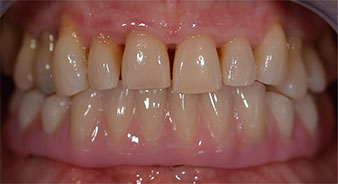

The 64-year-old patient presented with residual dentition of teeth 38, 33 and 43 and a clasp denture in the mandible (Fig. 1 and 2).